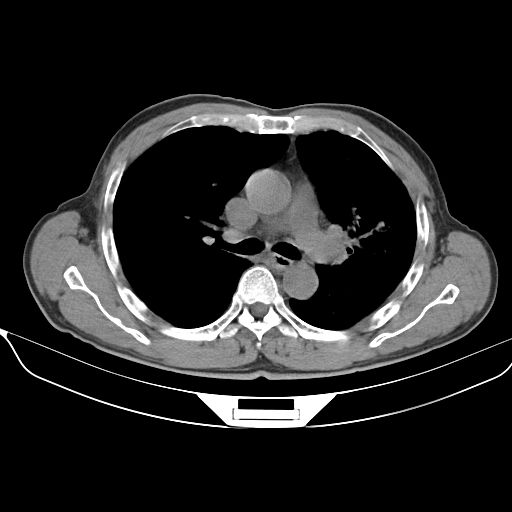

以下是引用心路寻觅在2010-3-1 10:23:00的发言:[br]1、考虑左肺上叶周围型肺癌[br]2、右上肺陈旧性病灶。[br][br][本贴已被 心路寻觅 于 2010-3-1 10:40:18 修改过]

以下是引用shuiyuan在2010-3-1 10:45:00的发言:[br]考虑左肺上叶中心型肺癌伴阻塞型炎症,邻近胸膜受侵。